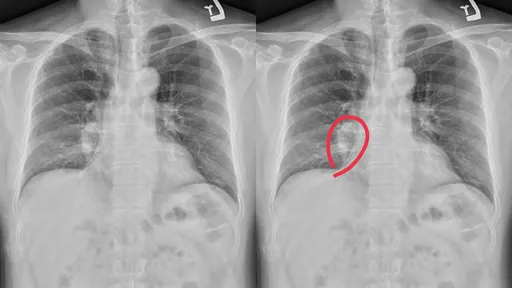

...,其中「肺腺癌」是最常见、也最棘手的类型,被医界称为「最恶霸癌王」,不少患者在不吸烟的情况下仍中镖。

...,让众人感到错愕,事实上,在台湾,肺癌被称为「三冠癌王」,因为它是癌症中发生人数最多、晚期确诊比例最...

...是发生人数最多、晚期确诊比例最高、死亡率最高的三冠癌王。 监委田秋堇、蔡崇义今天透过新闻稿表示,政...

【记者黄泓哲/综合报导】卫福部公布最新「111年癌症登记报告」,国人罹癌人数再攀新高,肺癌连续2年居首位,大肠癌位居第2,女性乳癌则排第3。由于癌症初期通常没有明显症状,容易被忽略,根据统计,111年新发癌症人数高达13万293人,较110年增加8,531人,标准化发生率为每10万人323.3人。

【记者黄泓哲/综合报导】在台湾,肺癌被称为「三冠癌王」,因为它是癌症中发生人数最多、晚期确诊比例最高...

...泓哲/台北报导】台湾肺癌是发生率和死亡率双冠的「新癌王」,且临床发现有一群病友过去仅有化疗可用、预后...